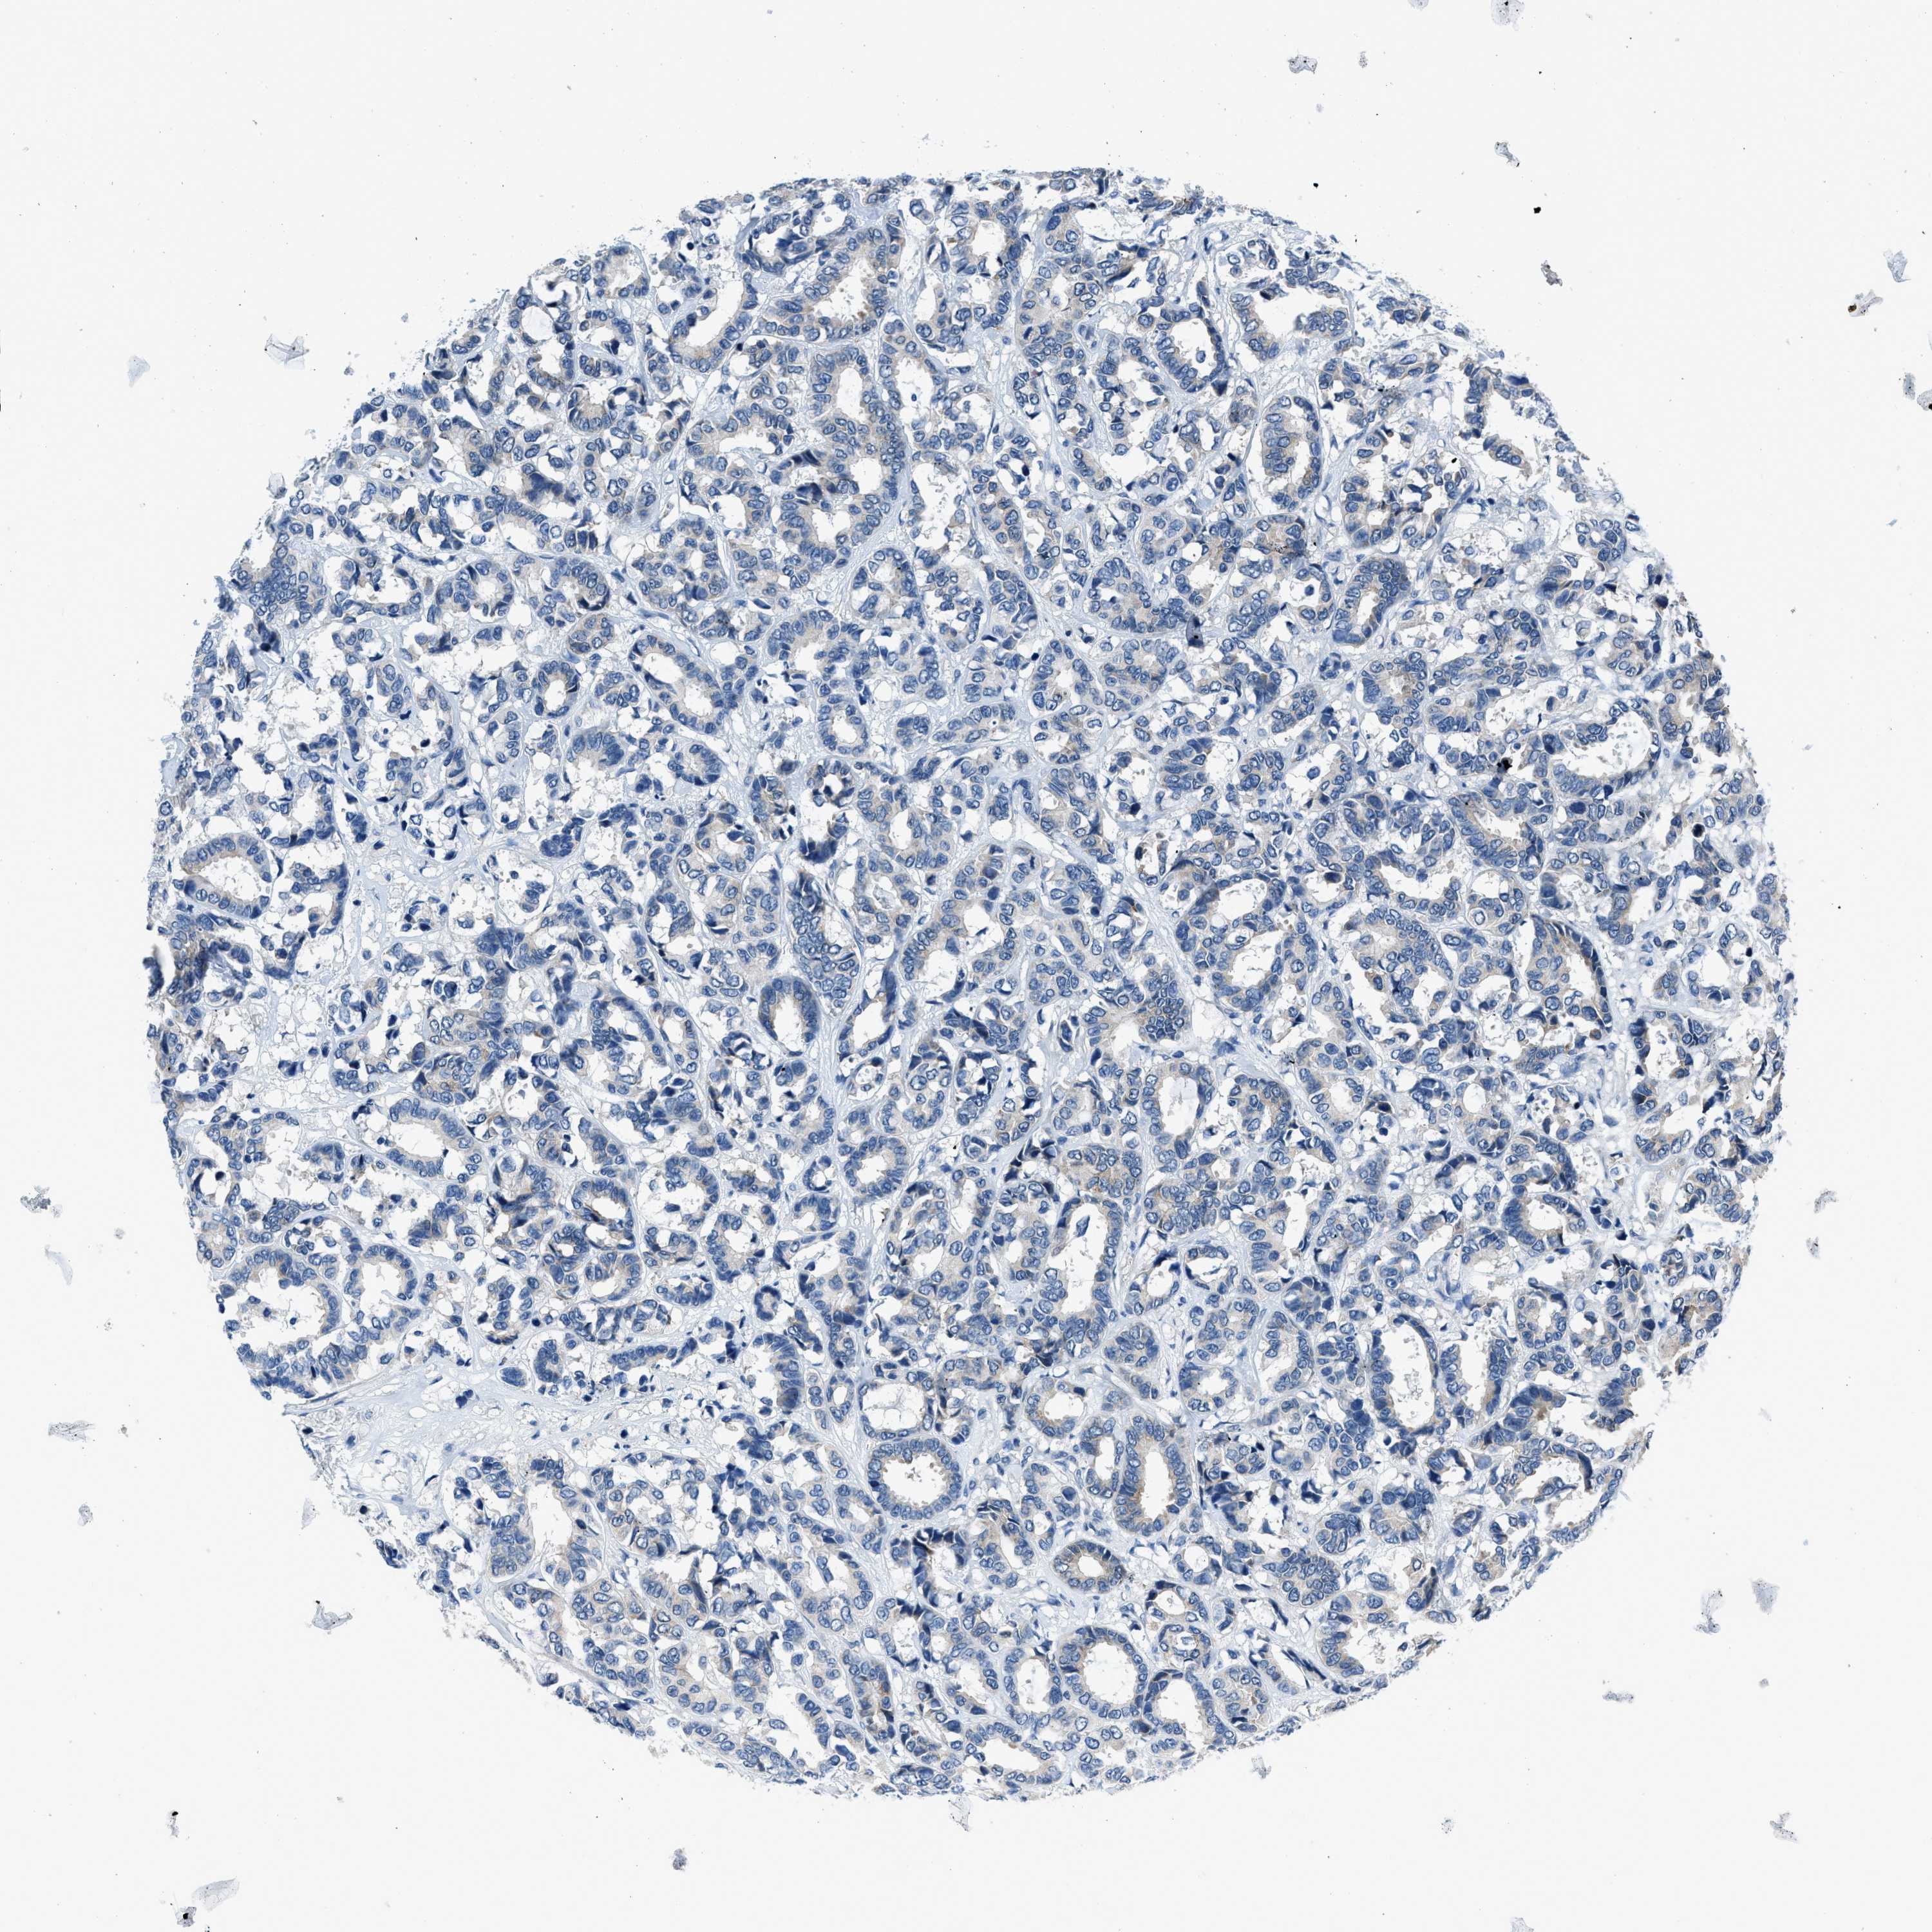

CANCER BREAST CANCER Show tissue menu

BRCA TCGA BRCA VALIDATION PROTEIN EXPRESSION